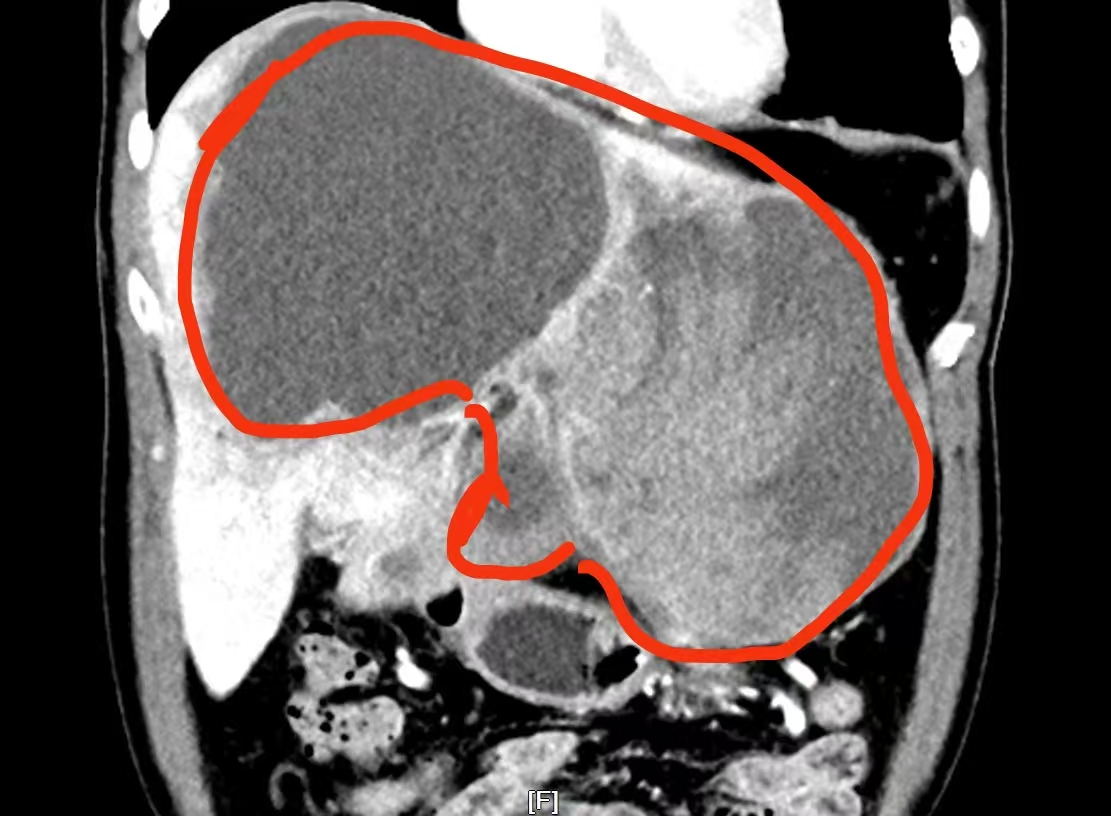

按照胃病治疗一段时间后,刘先生的症状不但没有好转,反而越发吃不下东西,只得利用国庆长假回到老家进一步检查。当CT结果出来后,刘先生如遭晴天霹雳——在他的胃和肝脏之间有一个22×21×14厘米的巨大肿瘤!正是由于肿瘤挤压胃部,才导致他进食困难、吃啥吐啥。

(▲影像资料显示:巨大的肿瘤占据了刘先生整个肝脏的三分之二。)

专家团队一致认为:巨大的肿瘤占据了患者整个左肝以及右肝前叶,手术操作空间极为狭小;加上肿瘤内部出血超过2000毫升,面对血供如此丰富的肿瘤,手术操作必须十分精准,否则极可能引发术中大出血,甚至危及生命;此外,在术前的下肢深静脉血栓筛查中,患者被发现有右下肢静脉血栓。为防止术中、术后出现致命性肺栓塞,介入血管外科医生为他放置了血管滤器。